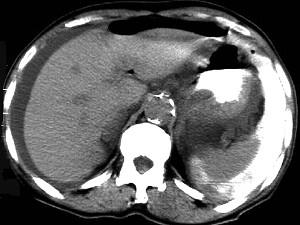

问题 男,44岁,突然中上腹痛,压痛,反跳痛,腹肌紧张,发热,白细胞计数升高,CT检查如图,最可能诊断是 ( )

选项 A、胰腺癌 B、胃癌 C、慢性胰腺炎 D、胃小弯溃疡穿孔 E、急性胰腺炎

答案 D